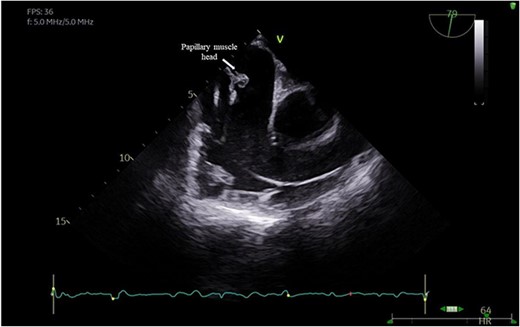

A 29-year-old man with a history of ventricular septal defect closure as a child, presented with severe multi-organ injuries after being run down by two cars. He was intubated on the scene by the hospital emergency medical services before being taken to the emergency department for haemodynamic stabilization and multiple imaging procedures. He suffered extensive bilateral degloving scalp lacerations and a haematoma due to bleeding from his left temporal artery. Computed tomography scan revealed bilateral multilevel rib fractures, a left-sided flail segment, bilateral haemopneumothoraces, and multifocal lung contusions, for which bilateral intercostal chest drains were inserted. Moreover, he had a shallow pneumopericardium, a subcapsular left renal haematoma, an extraperitoneal pelvic hematoma, displaced right-sided superior and inferior pubic ramus fractures as well as slight diastasis of the left sacroiliac joint. Although maximum resuscitation measures were taken with adequate fluid and blood product resuscitation, he remained persistently hypotensive and had worsening haemodynamics despite maximal inotropic support. A transoesophageal echocardiogram demonstrated a flail anterior leaflet of the TV and ruptured papillary muscle head (Fig. 1) with torrential tricuspid regurgitation (TR) and high right atrial (RA) pressures (Fig. 2).